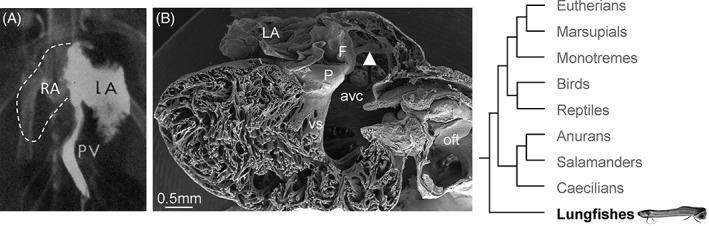

The complete division of the atrial cavity by a septum, resulting in a left and right atrium, is found in many amphibians and all amniotes (reptiles, birds, and mammals). Surprisingly, it is only in eutherian, or placental, mammals that full atrial septation necessitates addition from a second septum. The high incidence of incomplete closure of the atrial septum in human, so-called probe patency, suggests this manner of closure is inefficient. We review the evolution and development of the atrial septum to understand the peculiar means of forming the atrial septum in eutherian mammals. The most primitive atrial septum is found in lungfishes and comprises a myocardial component with a mesenchymal cap on its leading edge, reminiscent to the primary atrial septum of embryonic mammals before closure of the primary foramen. In reptiles, birds, and mammals, the primary foramen is closed by the mesenchymal tissues of the atrioventricular cushions, the dorsal mesenchymal protrusion, and the mesenchymal cap. These tissues are also found in lungfishes. The closure of the primary foramen is preceded by the development of secondary perforations in the septal myocardium. In all amniotes, with the exception of eutherian mammals, the secondary perforations do not coalesce to a secondary foramen. Instead, the secondary perforations persist and are sealed by myocardial and endocardial growth after birth or hatching. We suggest that the error-prone secondary foramen allows large volumes of oxygen-rich blood to reach the cardiac left side, needed to sustain the growth of the extraordinary large offspring that characterizes eutherian mammals. Anat Rec, 302:32-48, 2019. © 2018 The Authors. The Anatomical Record published by Wiley Periodicals, Inc. on behalf of American Association of Anatomists.